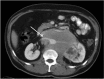

Patients with retroperitoneal sarcoma can present to a variety of clinicians with non-specific symptoms and retroperitoneal sarcomas can be incidental findings. Failure to recognize retroperitoneal sarcomas on imaging can lead to inappropriate management in non-specialist centers. Therefore it is critical that the possibility of retroperitoneal sarcoma should be considered with prompt referral to a soft tissue sarcoma unit. This review guides clinicians through a diagnostic pathway, introduces concepts in response assessment and new imaging developments.